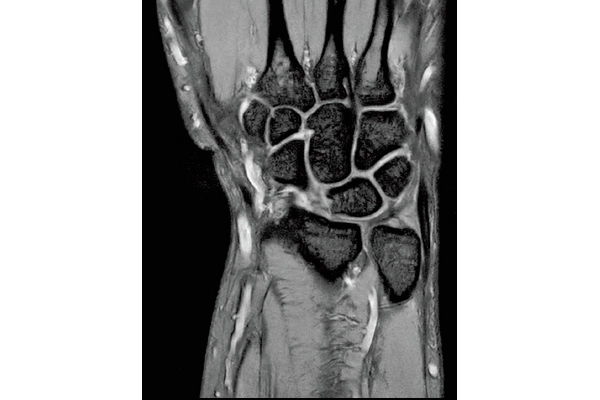

3D Bone

0.93×0.93×1.2(0.6)mm

1.1×1.1×1.2(0.6)mm

3DisoFSE T2WI

0.75×0.75×1.1(0.55)mm

MPR COR